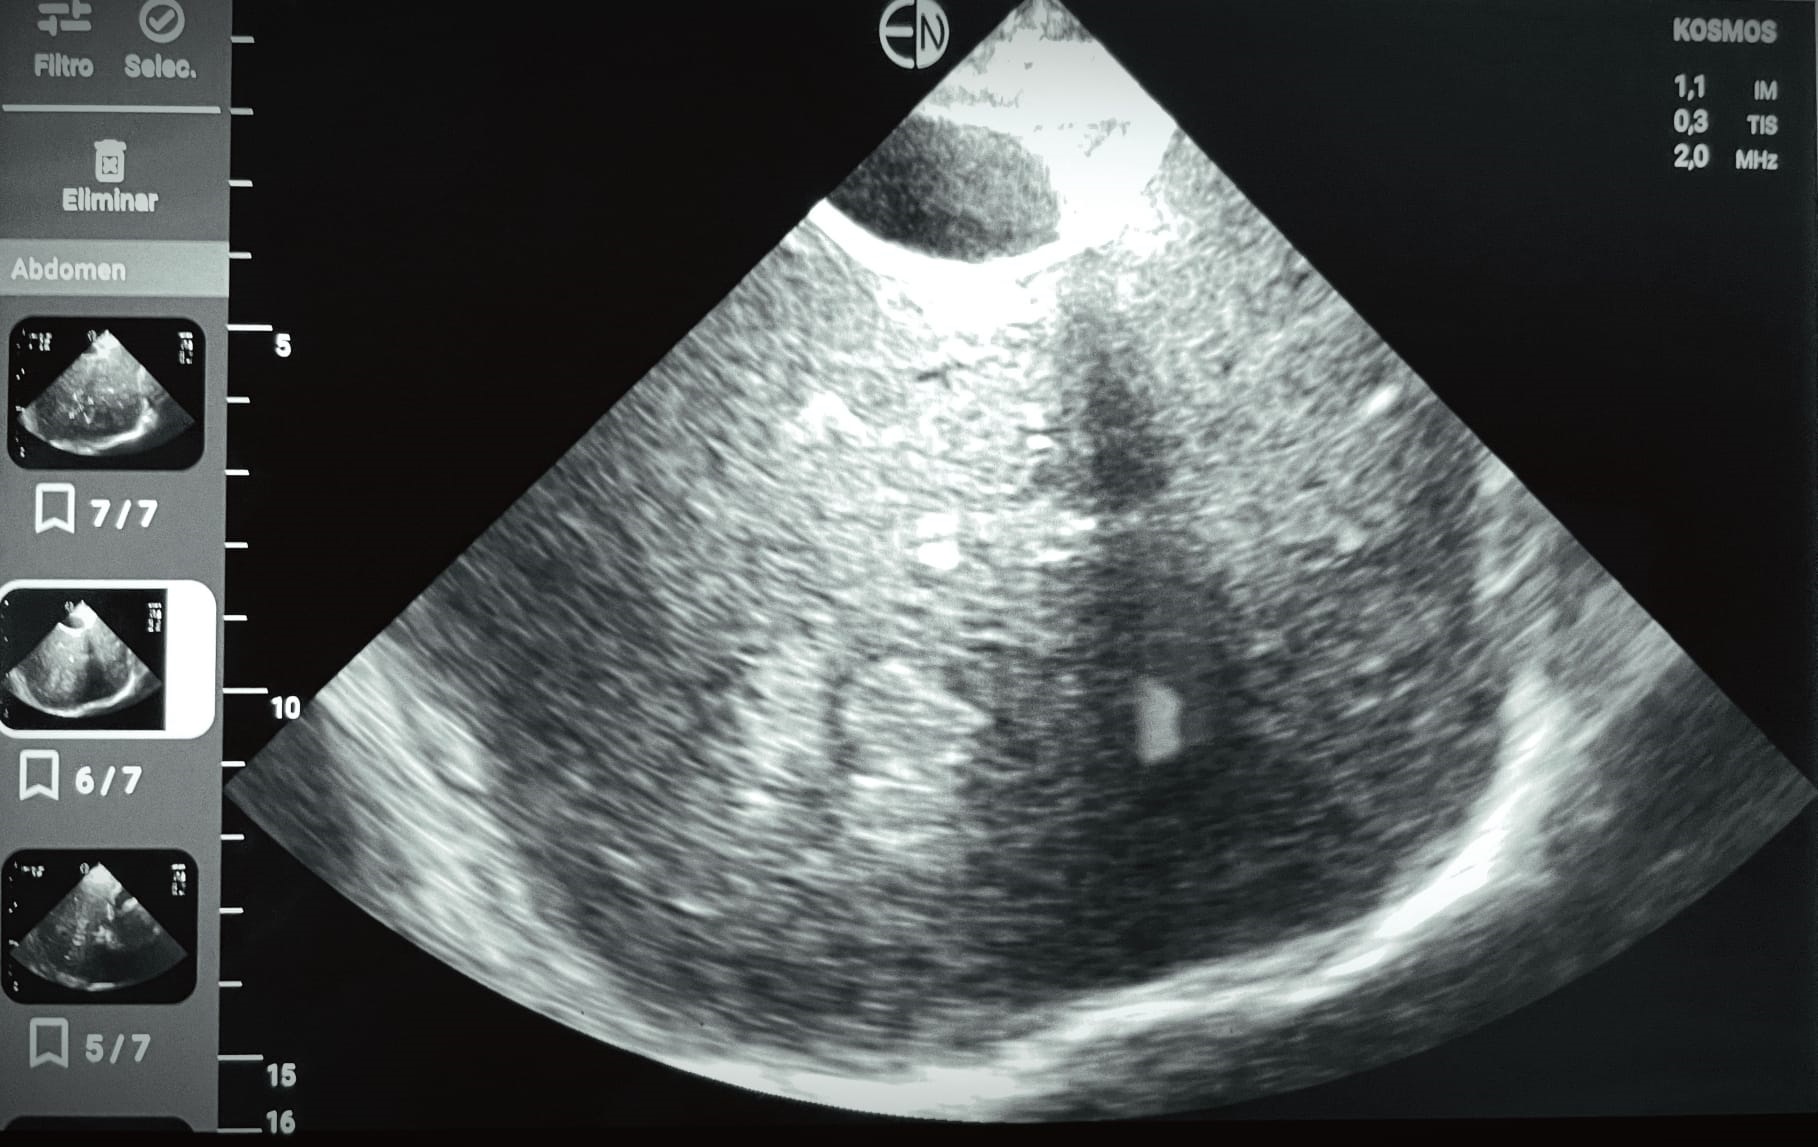

Ecografía POCUS abdomen: se identifican al menos dos imágenes hiperecogénicas en parenquima hepático, con regiones de aspecto algo heterogéneo, la mayor de ellas de 4,9 cm diámetro máx. No líquido libre. Vesícula distendida, sin signos de colecistitis o dilat vía biliar.